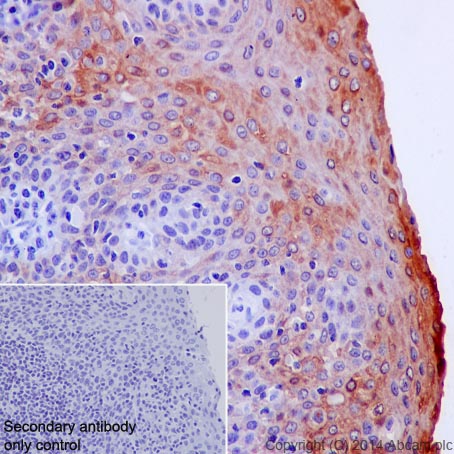

Immunohistochemistry (Formalin/PFA-fixed paraffin-embedded sections) - Anti-Cytokeratin 6 antibody [KRT6/1702] (AB218438)

Immunohistochemical analysis of formalin-fixed, paraffin-embedded human bladder carcinoma tissue labeling Cytokeratin 6 with ab218438 at 0.2 μg/mL.